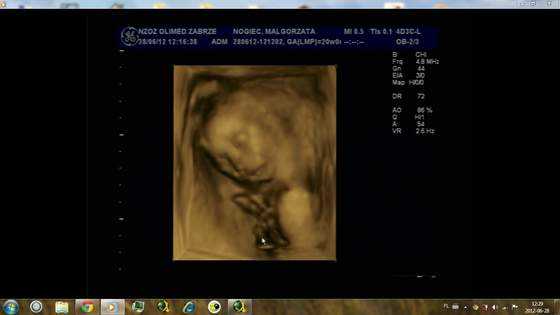

Natkusia!!! ojoj!!! wow!!!! trzymam kciuki!!! &&&&& Ty już rodzisz prawie że :-)

gochaa piękny ten Twój Mateuszek

super, że już macie pewność że to chłopczyk